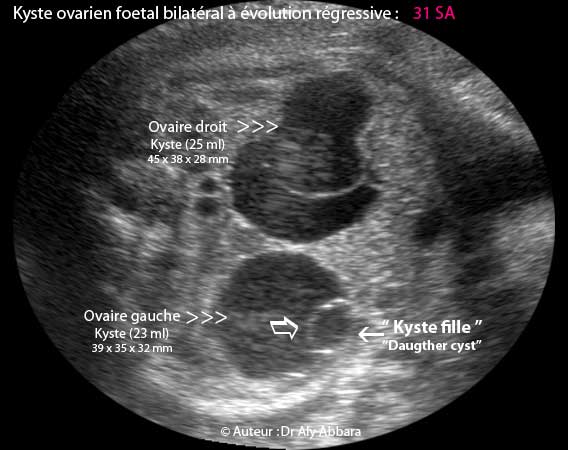

Kyste De L Ovaire Foetal Bilateral Et Regressif In Utero

Kyste De L Ovaire Fœtal Bilateral Et Regressif In Utero